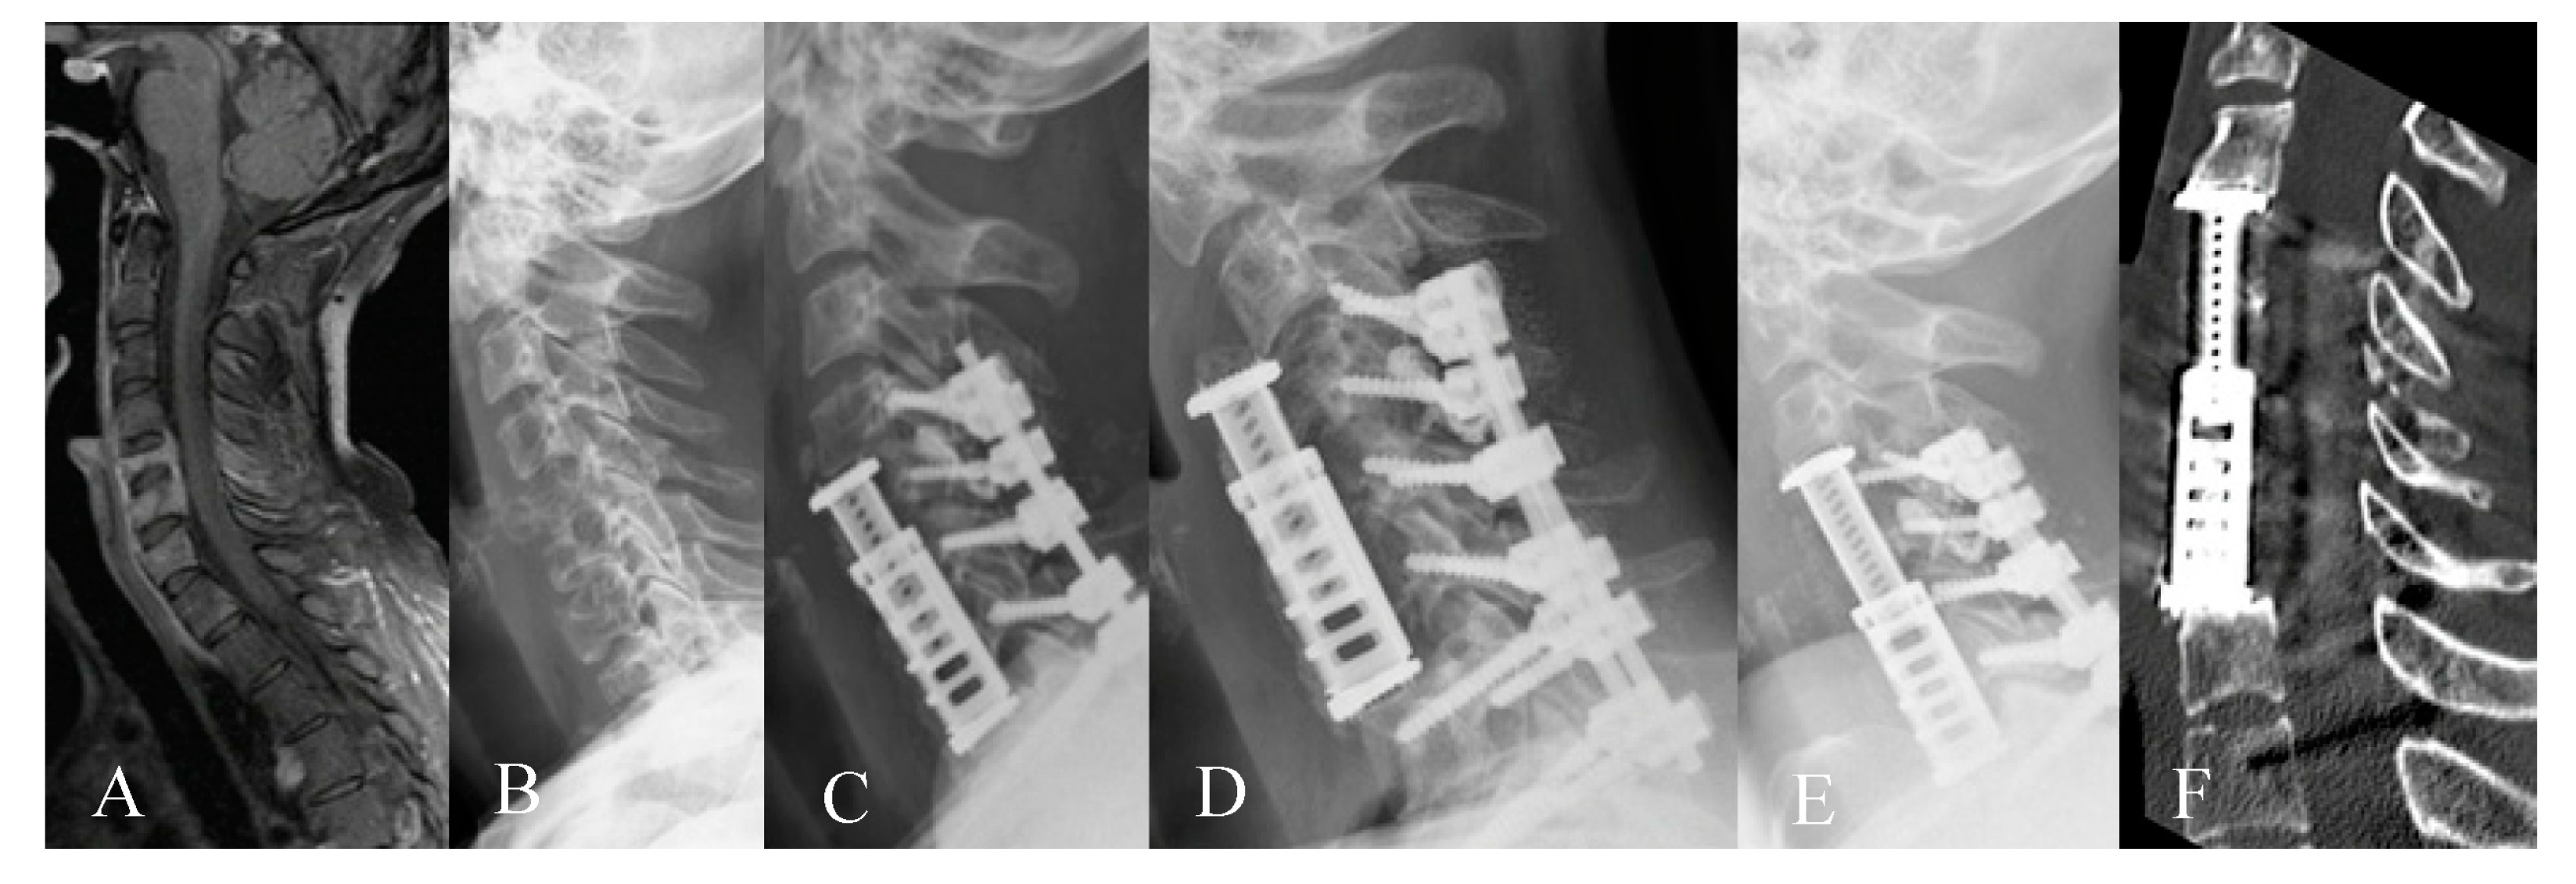

3.2. Radiological Outcome

3.3. Complications